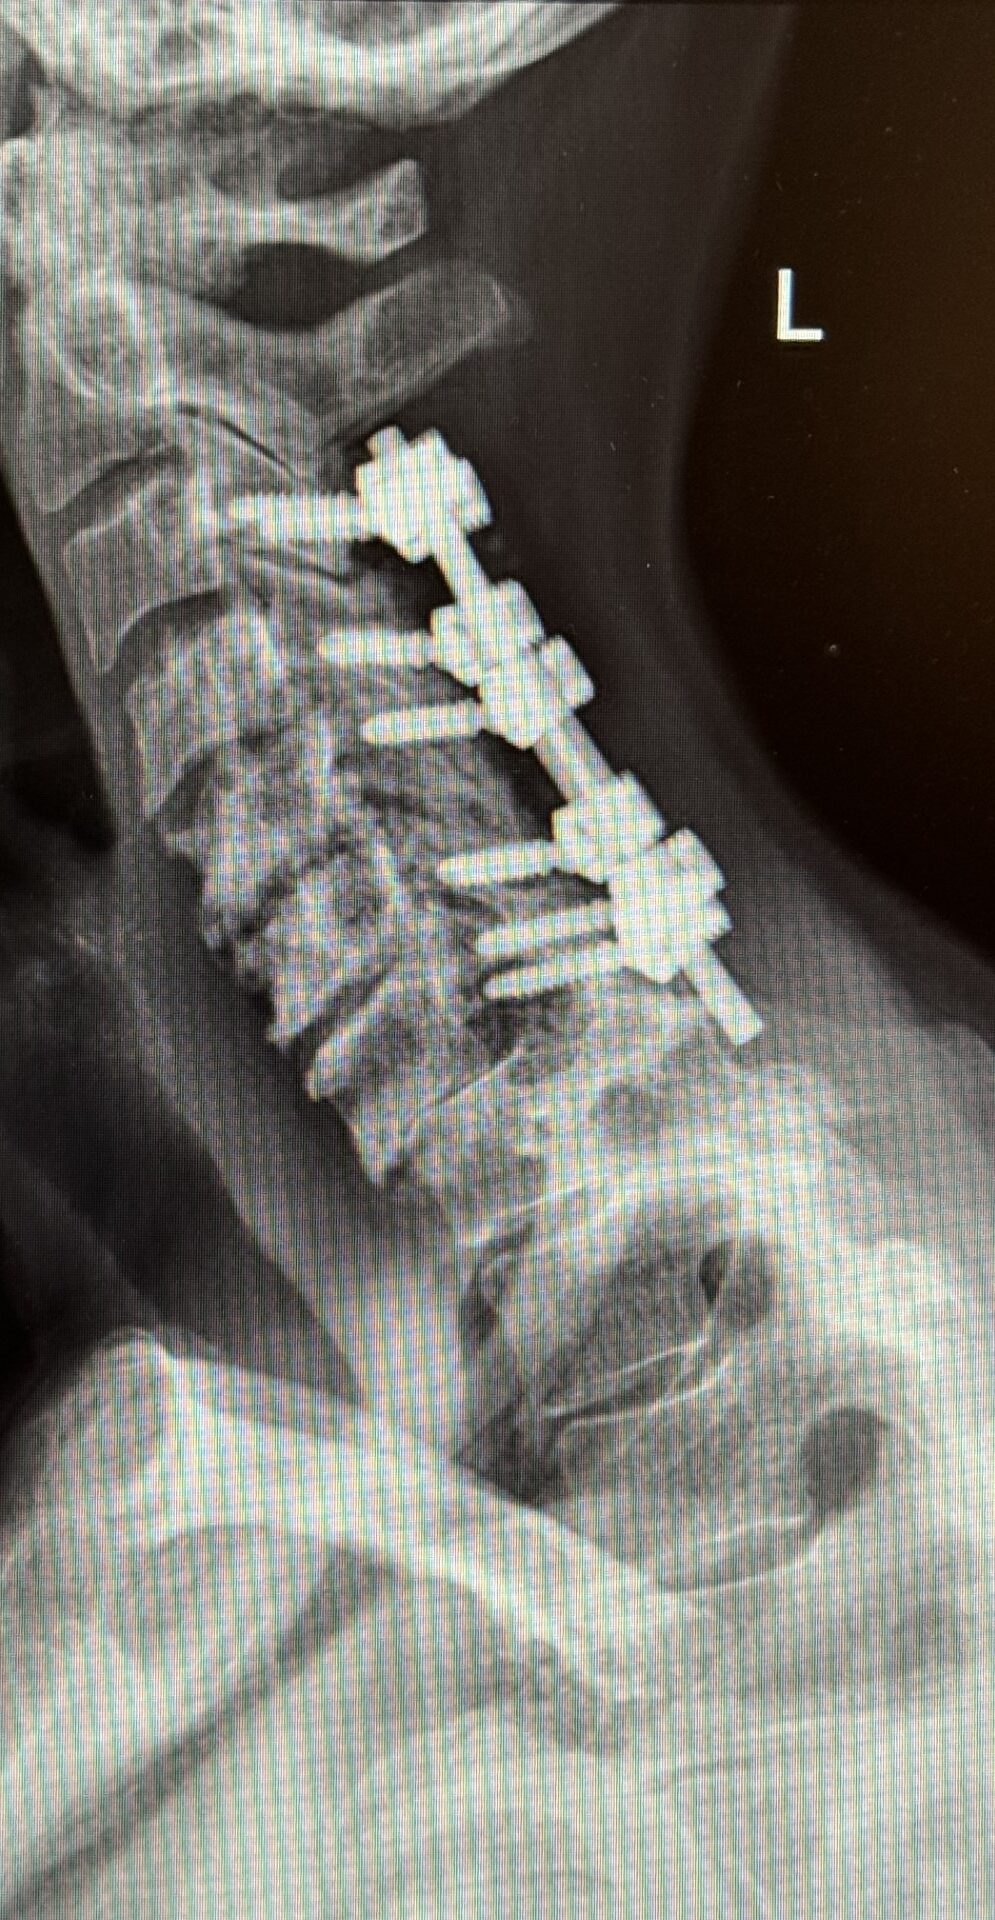

The patient is a 61-year-old female with a history of rheumatoid arthritis. She is 2-1/2-years status post C3-C7 laminectomy with posterior instrumentation and fusion. This procedure was performed to treat multilevel disc herniations with spinal cord compression following a motor vehicle accident.

Her rheumatologist ordered an x-ray which showed anterolisthesis of C7-T-1 with kyphosis and instability (Fig 1 right).

The patient underwent a one-day, two-stage procedure. Stage 1 was a C6-7, C7-T1 anterior cervical discectomy and fusion with reduction of the anterolisthesis and correction of the kyphosis.

Stage 1 was immediately followed by Stage 2 which was extension of her posterior instrumentation and fusion from C3 down to T3. Neuro-navigation was used to assist with the difficult anatomy of the upper thoracic spine.